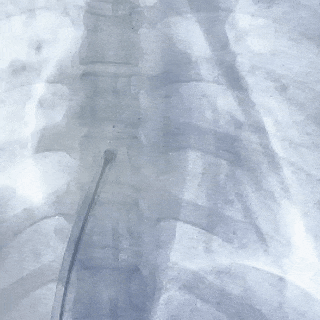

左盘面展开

前推钢缆,后撤鞘管,使左盘面3个Mark点及腰部显影点推送至鞘管外,并牵拉成型线

将封堵器和输送系统整体后撤,使左盘面贴合房间隔

右盘面展开

后撤鞘管,前抵钢缆释放右盘面